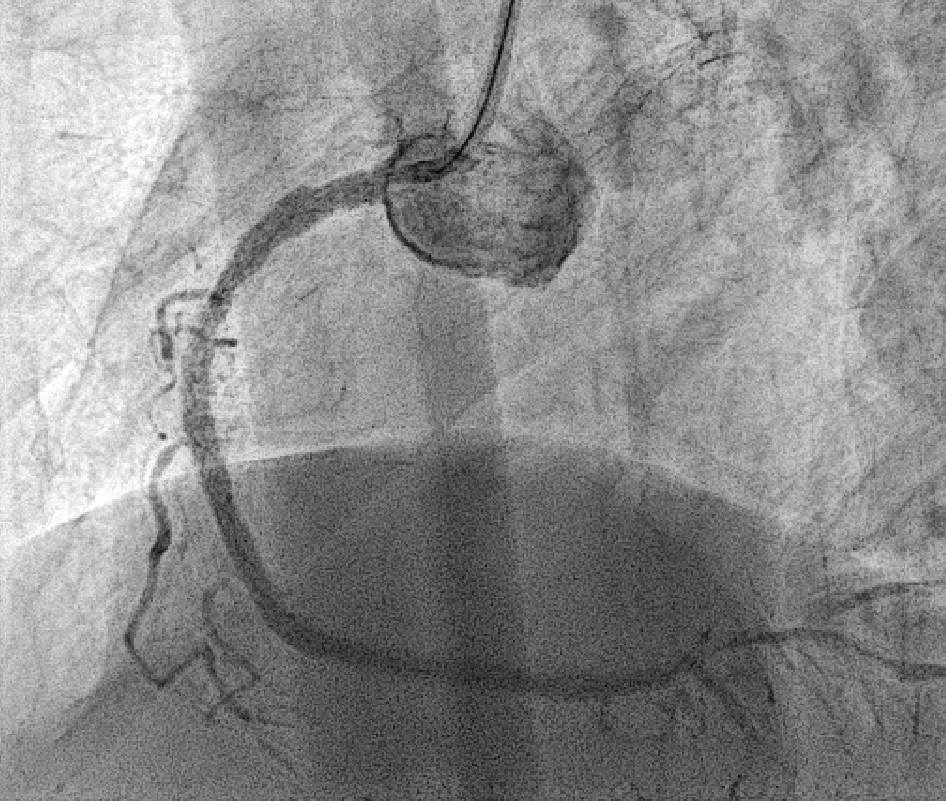

Coronary angiography revealed 81% in-stent restenosis at the right coronary artery ostium, worsened since February 2025. Proximal and mid RCA stents were patent; distal RCA was patent but smaller in caliber . Left main and LAD stents showed no progression, though 30–60% restenosis was seen in proximal to mid LAD. Left circumflex artery was nearly totally occluded from ostium to proximal segment, with preserved flow in mid and distal segments, similar to prior study.

We advanced a 6F JR 4.0 SH 100cm guiding catheter and crossed the RCA ostial lesion using a Fielder FC guidewire. Pre-dilatation was performed with Ryurei 1.5¡¿15mm balloon. IVUS was then performed, revealing a patent stent in the proximal to mid RCA. However, the ostial RCA stent was under-expanded, with smooth muscle compressing the stent from outside. Balloon pre-dilatation was carried out using an NC Euphora 4.0¡¿12mm balloon, inflated up to 22 bar. However, the lesion was resistant and could not be fully dilated. We then applied a 4.0mm intravascular lithotripsy balloon with a total of 100 shocks delivered. But the effect was still minimal. The IVUS showed limited additional plaque fracture or vessel expansion. We tried NC Sapphire II 4.5¡¿8 mm balloon inflation to 18 bar, but it was ineffective due to balloon slippage. The angiogram after oversized NC dilation showed residual stenosis of 59%. We then selected a Wolverine Cutting Balloon 4.0¡¿10 mm and initiated dilation to 6 bar, which resulted in easy slippage again. Subsequent oversized dilations were performed at 18 bar, after which the lesion was successfully dilated. Using a Runthrough Floppy guidewire with the floating wire technique, a drug-eluting stent Biofreedom Ultra 4.0¡¿14 mm was deployed in the ostial RCA ISR. We inflated at 14 bar for 14 seconds, repeated twice. Final post-dilatation was performed with an Accuforce 4.0¡¿15mm balloon. The final IVUS showed good stent placement and expansion. We closed the procedure.

Case Summary